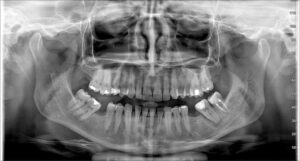

Fotografimi i dhëmbeve- Ortopani

- Rëntgeni Ortopan, mundëson identifikimin mjaftë të suksesshëm të dhëmbëve, të nofullës së poshtme dhe të sipërme, si dhe formacionet patologjike të kockave të nofullës.

- Karakteristika më e rëndësishme është zbulimi i të gjitha detajeve që janë të pamundur të vërehen përmes shikimit me sy si dhe kontribojnë në diagnostikimin dhe trajtimin e saktë nga mjeku.

- Për këtë arsye pas ekzaminimit të parë të pacinetit sipas kërkesave shërben si një prej metodave më të kërkuar në drejtim të përcaktimit të trajtimit.